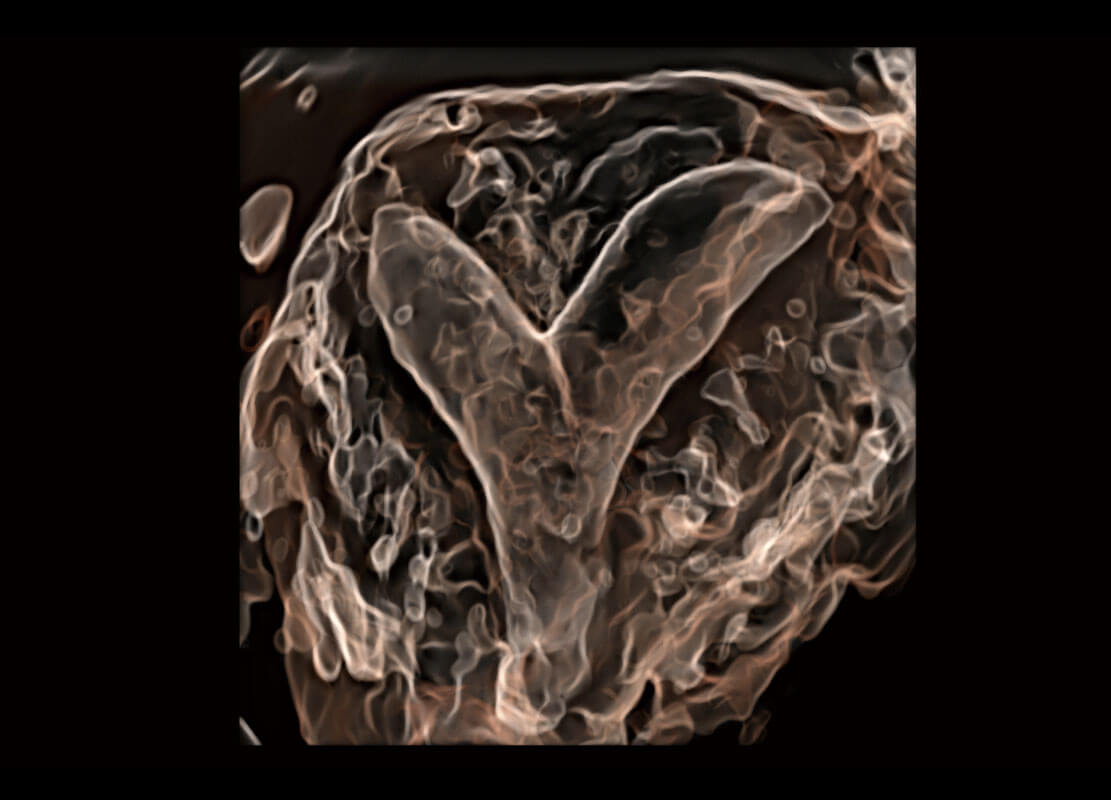

• 腔内三维-宫内节育器

• 腔内三维-光影成像

生殖健康

P60优异的图像质量搭载专科探头,在妇科基础疾病的诊断、卵泡生长的监测、输卵管通畅情况的判别等方面为您提供生殖应用方案。